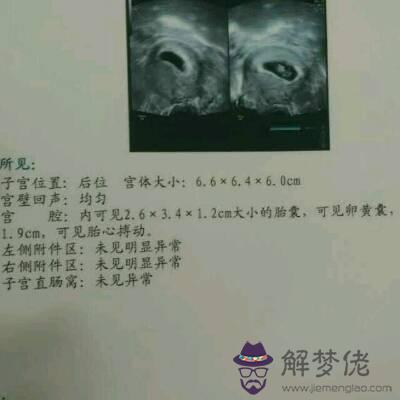

2、懷孕多久可以看出性別:幫忙看看四維單子是男是女謝謝

你好,看四維B超檢查報告,但是不能確定男孩女孩的這個準確性太差了,沒有什麼科學道理。

3、懷孕多久可以看出性別:四維單子可以看出男孩女孩嗎?

你好,根據這個四維彩色超聲檢查結果,是不能確定男孩女孩的,沒有什麼準確性。